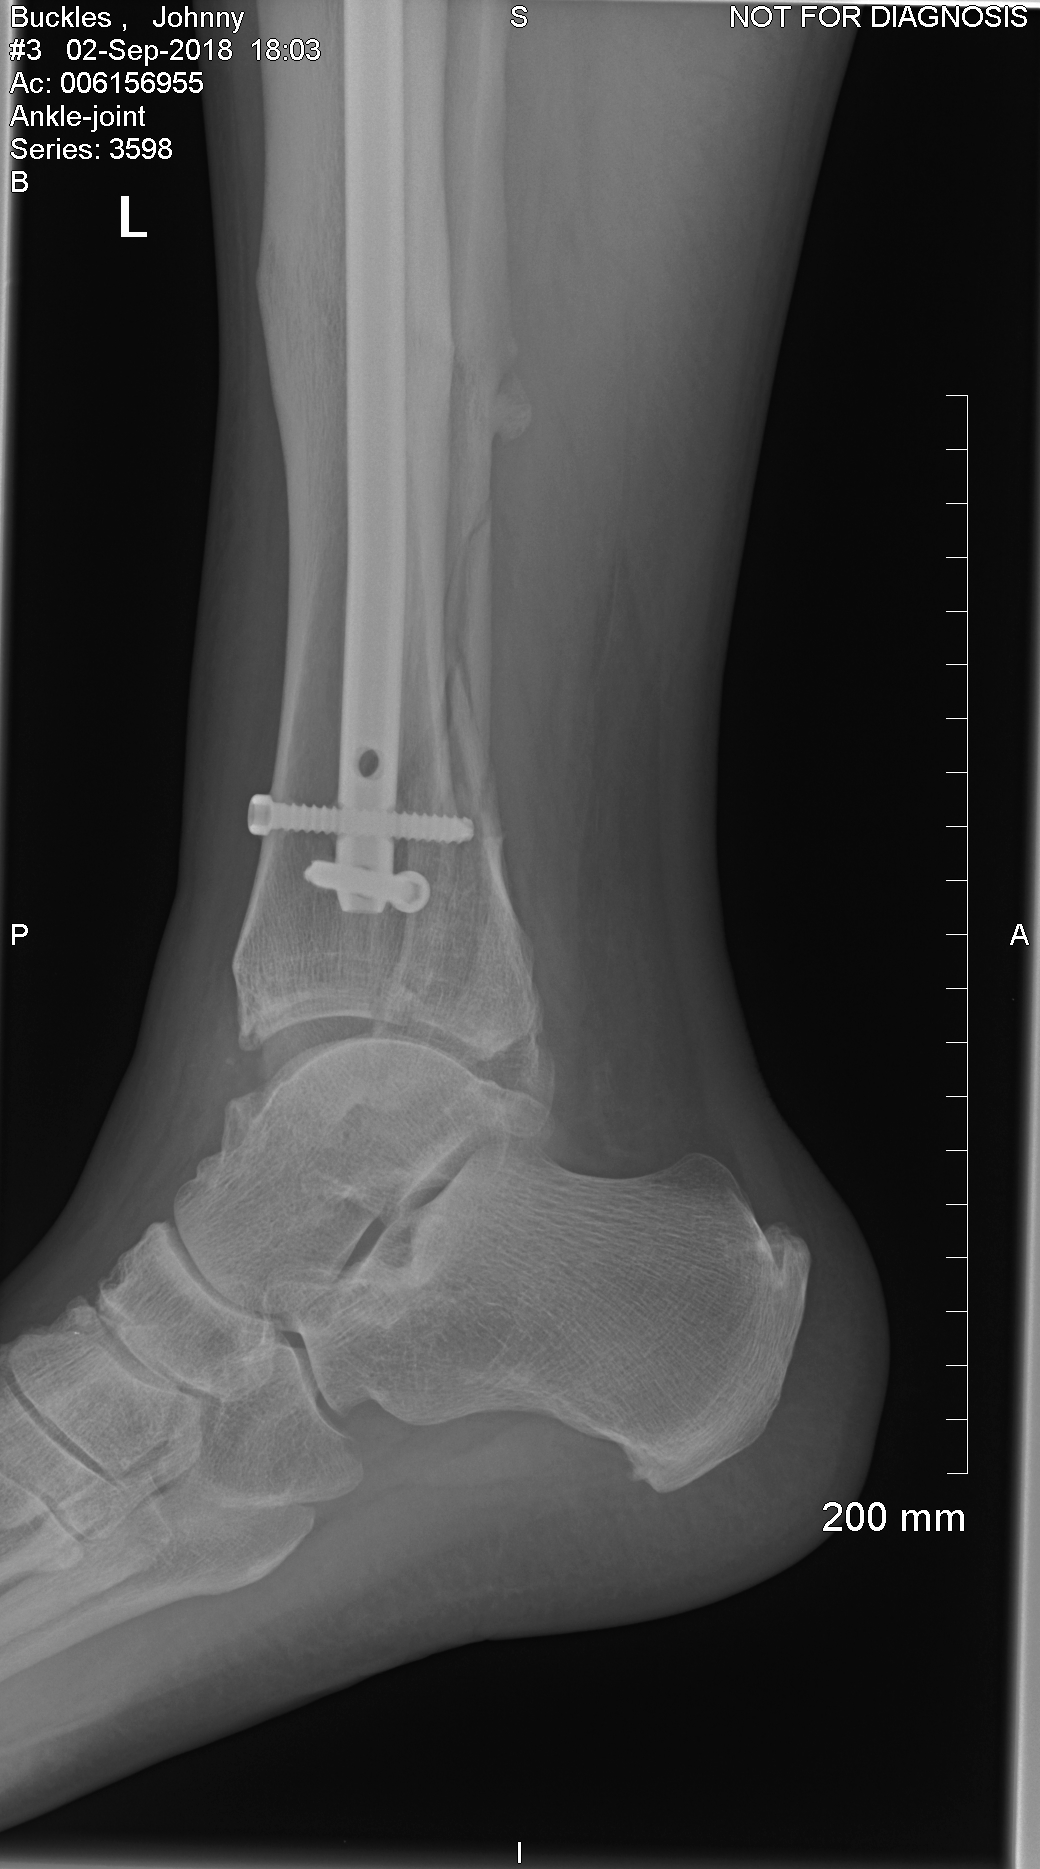

This is the same leg I broke in 2009 in 7 places and this time I broke the fibula cracked the tibular and broke the ankle I screamed like a 10 year old girl lol.

I had a cat scan done yesterday and went to doctor for results and he said the ankle has broke into and will need surgery Thursday he is going to take out 1 screw from the last surgery I had on this leg and put a plate in and 4 more screws.

Doctor said it was broken worse than first thought and had to use 9 screws and a plate to get the bones back together.